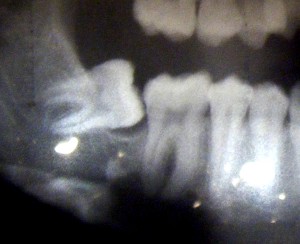

Here is the x-ray -

Apparently my bottom 12 year molars never came in, and my wisdom teeth are filling in for them...side ways.

My mouth is incredibly small, apparently. In-cred-i-bly small. Can you imagine if my 12 year molars had come in, too?

Obviously, my teeth can’t stay like that. Instead of pulling them, which would change the shape of my face, they are going to pull them back into place.

Pretend the blue oval is a metal rod with a spring on it that will pull my molars back into place. Dr. Brooks will insert the rod onto my tooth and attach that to my jaw bone so it will be pulled back into place. Sounds gruesome, eh? =) But it’s not, really.